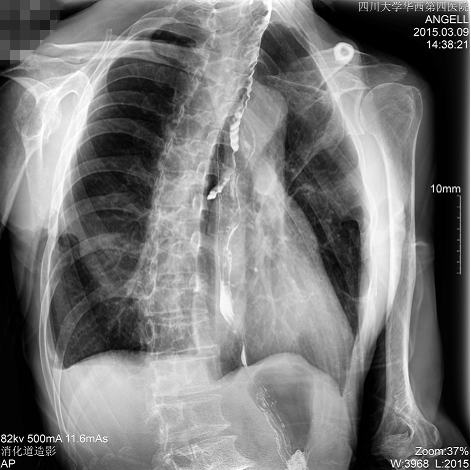

图为斜位:通过动态影像可以清楚看到钡剂进入了支气管道

通过多功能dr可以诊断该病人的症状为会厌功能紊乱,钡剂进入到了气管。而在动态透视下可以清晰的观察到钡剂从何处进入气管,可清晰显示食管粘膜结构。使用多功能dr其独特的视频采集技术,可实时保存视频并能实现900万像素实时点片,才能获取这样清晰的病灶点。而常规dr只能拍摄静态片,且成像效果大打折扣,因此较难确诊病灶。